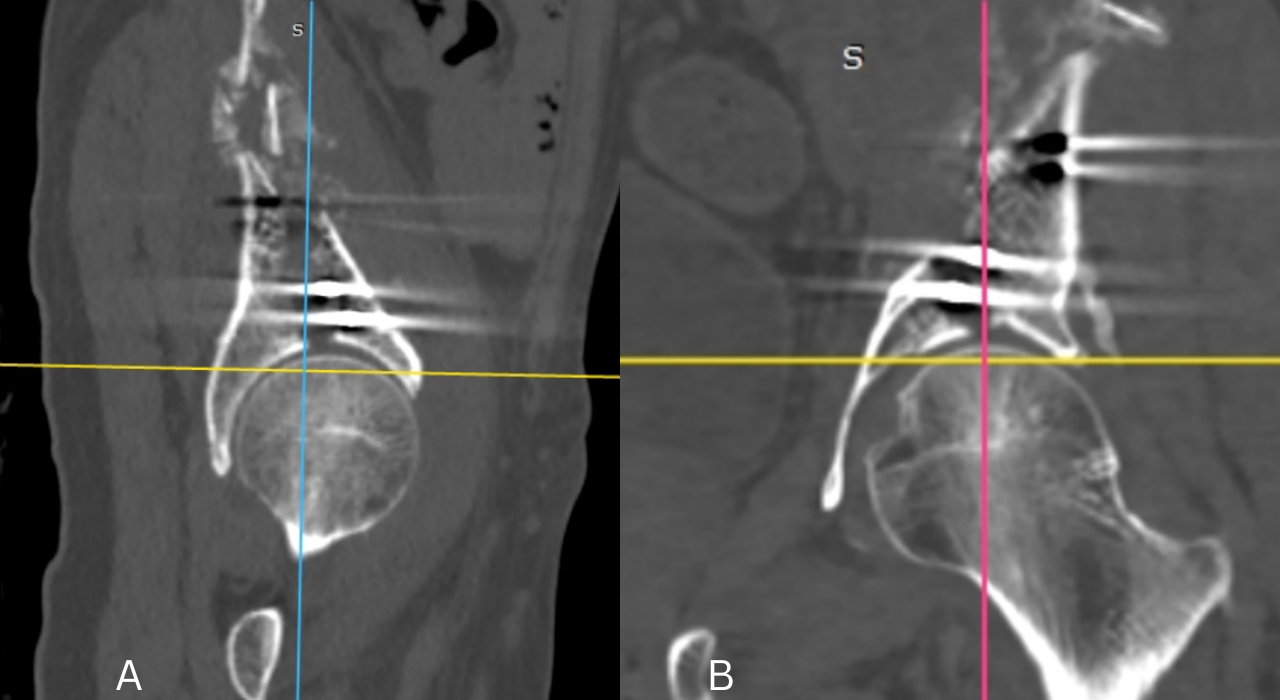

according to Letournel and Judet [2], detaching the acetabular roof and the adjoining part of the iliac wing while respecting the continuity of the pelvic ring (Fig. 2).

Figure 2: Post-operative computed tomography scan of fracture (a) Sagittal view (b) Coronal view.